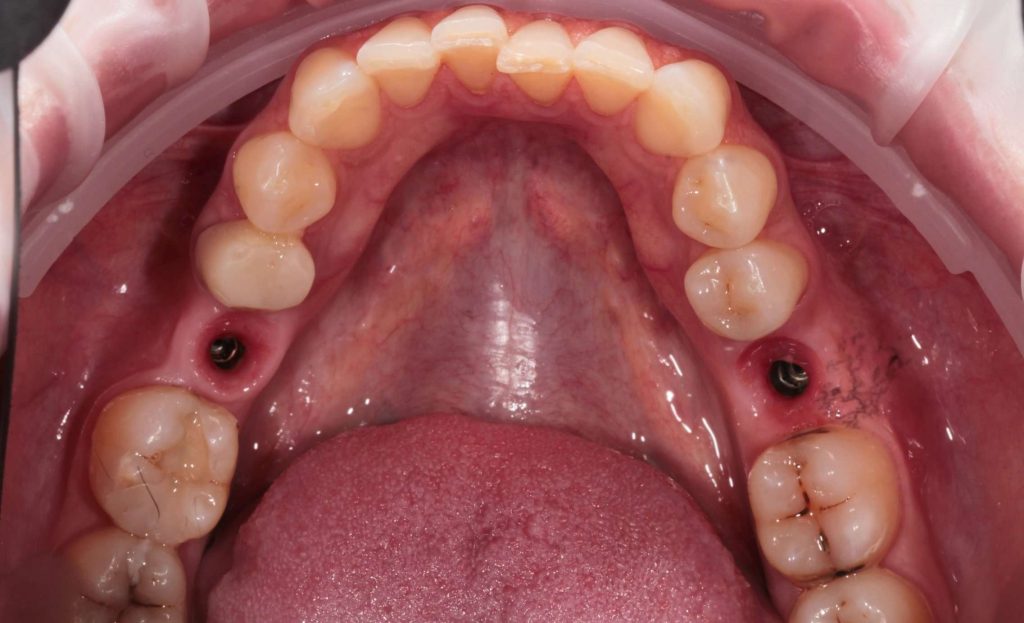

Отсутствие 2-х жевательных зубов на нижней челюсти

Отсутствие 2-х жевательных зубов на нижней челюсти. Большая пломба в зубе

Нижняя челюсть – было установлено 2 импланта и 2 коронки на импланты и 1 коронка на свой зуб.

- Установка имплантов и формирователей десны.